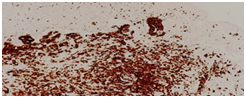

Maternal and family history was negative for syndromes or systematic diseases and with an uncomplicated prenatal course in a provintial hospital. On clinical examination was found large for gestational age neonate without pathological reason for that. Imaging and laboratory studies were performed, and were within normal limits. On the 4th day of life a biopsy from pediatric surgeons was performed by obtaining a specimen from the papule on the left cheek and sent for histopathological examination. The specimen measured 0.5X0.5X0.3cm. Hematoxylin and eosin stained sections showed a diffuse cutaneous infiltration by medium-sized to large cells with abundant cytoplasm and characteristic irregular, elongated or with prominent folds and grooves (Figure 2A). Immunohistochemistry was performed and the cells were positive to S-100 protein (Figure 2B), CD1a antigen (Figure 2C) CD68 and HLA-DR. The diagnosis of Langerhans cell histiocytosis was set.

Figure 2A Hematoxylin and eosin stained sections showed a diffuse cutaneous infiltration by medium- sized to large cells with abundant cytoplasm and characteristic irregular, elongated or with prominent folds and grooves nuclei.